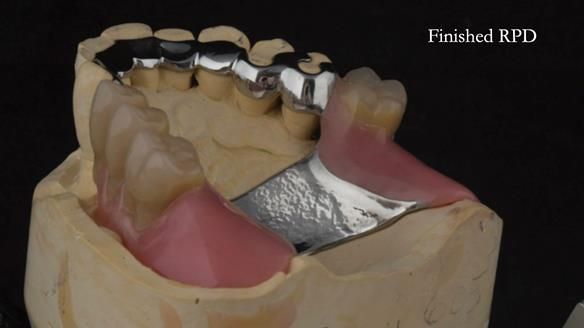

Instead, we made a Scandinavian-style, metal-based lower RPD.

It’s worth saying that the lower denture in this case was made in the early days of Rowan and me using the Scandinavian approach. Rowan cast the metalwork himself for this denture.

Looking back, we would make this denture more hygienic now. The design and finish would be more refined and delicate, particularly when compared with the upper metalwork, which was made later using Chris Hesketh’s chrome work. I will discuss this in detail at the study club.

That said, the lower denture worked beautifully. It did exactly what it was meant to do, even though, by today’s standards, it looks a little agricultural.

A metal-based upper RPD was made,

with metal backings incorporated to future-proof the design

should further teeth fail.